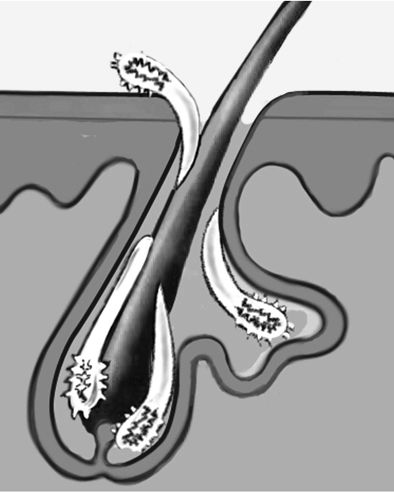

В етіології демодекозу ключову роль відіграють особливості будови волосяного фолікула, в якому знаходиться волосся, відкривається сальна заліза і її протоки. Скупчення шкірного сала створює найсприятливіші умови для розмноження кліща. Максимальна щільність сальних залоз знаходиться на шкірі обличчя (від 500 до 1000 на 1 квадратний см), що пояснює локалізацію висипань. Накопичуючись, кліщ закупорює сальну протоку, що провокує ще більше вироблення шкірного сала.

Паразитуючи в шкірі обличчя, кліщ демодекс харчується вмістом сальних залоз, клітинами епідермісу і кров'ю.